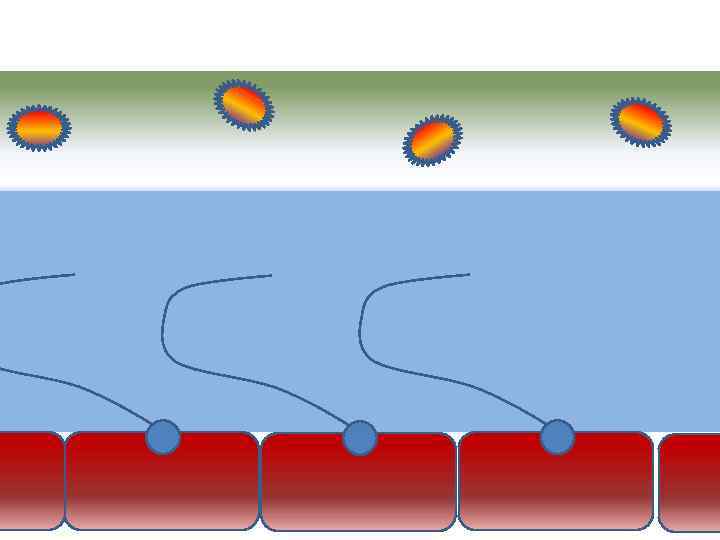

Движение клеток реснитчатого эпителия Движение вперед 1 – 3 Обратное движение 4 – 8

Движение клеток реснитчатого эпителия Движение вперед 1 – 3 Обратное движение 4 – 8

Механизм защиты легкого Слизь (зеленый цвет) нейтрализует и связывает патогенную флору(синий цвет) Слизь – это барьер между клетками и патогенной флорой Слизь – это транспортное средство

Механизм защиты легкого Слизь (зеленый цвет) нейтрализует и связывает патогенную флору(синий цвет) Слизь – это барьер между клетками и патогенной флорой Слизь – это транспортное средство